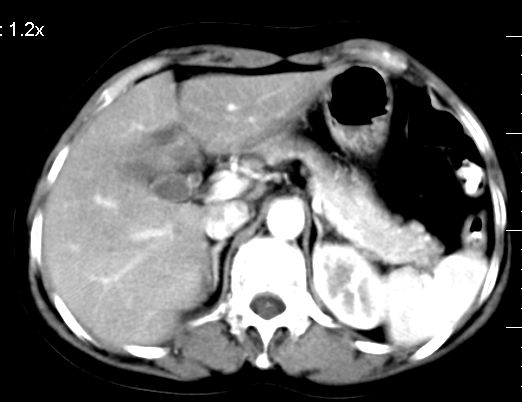

双肾灌注良好,代谢增快,动脉期肾盂见造影剂,左肾下极背侧见一略低密度病灶,延迟期见似不强化囊肿,双侧肾上腺未见异常。

胰腺及脾未见异常。肾门水平腹膜后见小淋巴结。腹腔未见积液征象。

3、左肾下极低密度灶,考虑囊肿可能性大,建议随访,除外小肾癌(无强化可以基本除外)。

肝顶处小血管瘤,左肾小囊肿

左肾下极低密度灶,考虑囊肿可能性大,建议必要时复查

肝圆顶部小血管瘤,左肾小囊肿

3、左肾下极囊肿.